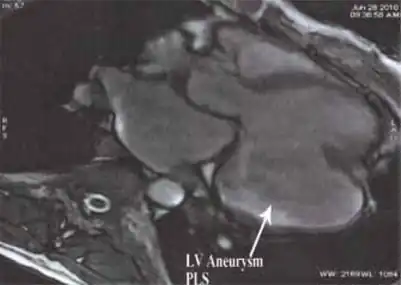

- MRI showing the posterobasal left ventricular aneurysm